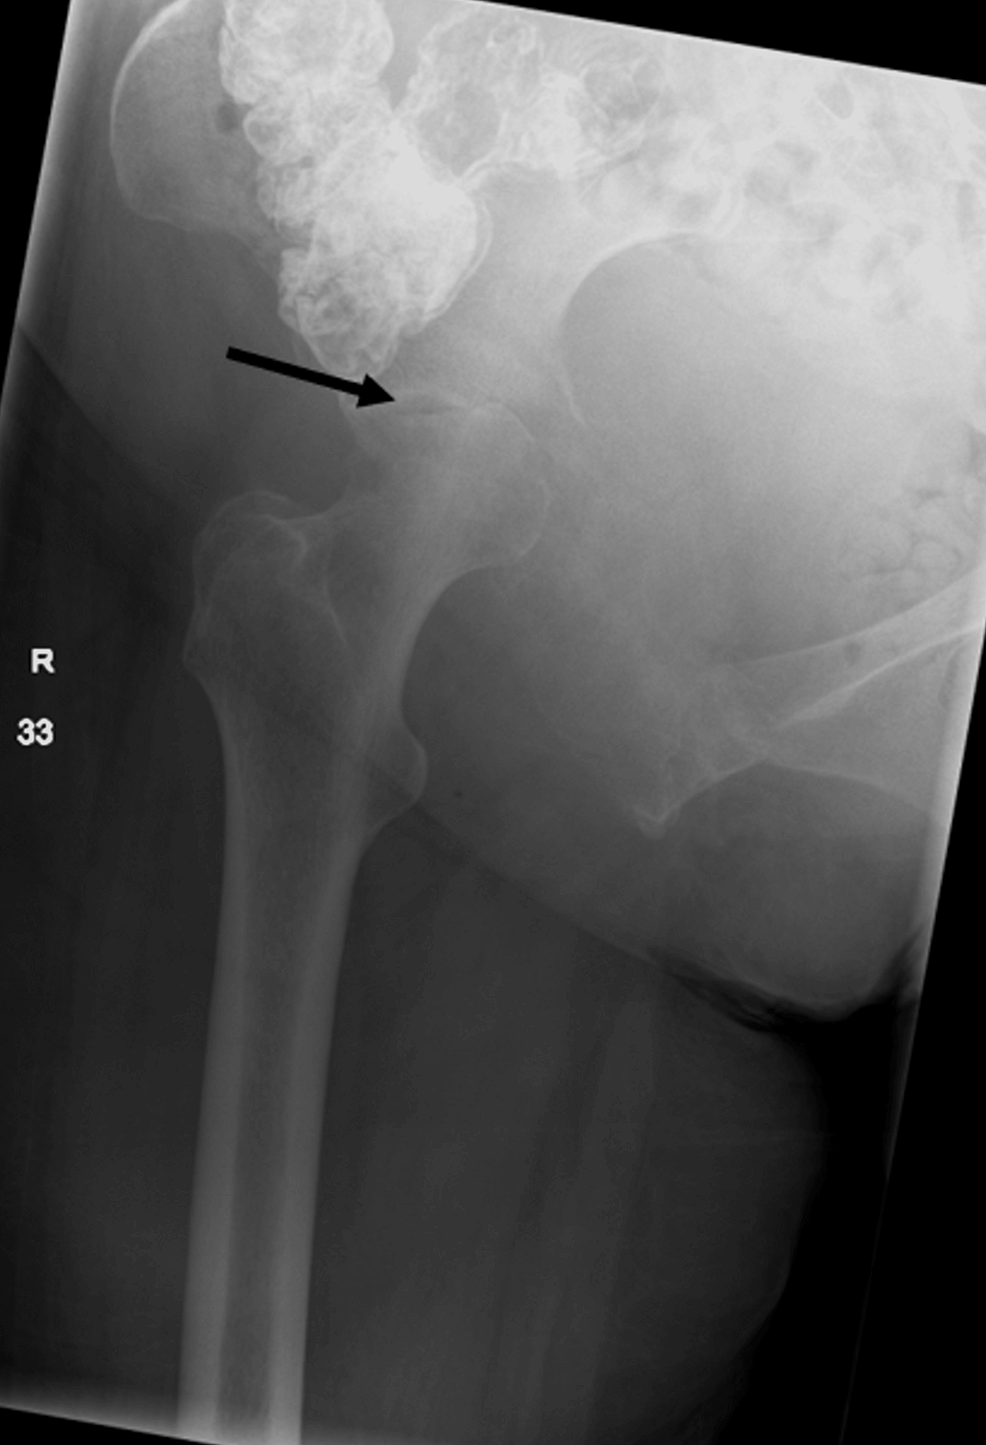

Bone marrow cancer, Xray Stock Image C020/7258 Science Photo Library

Bone marrow cancer, Xray Stock Image C020/7258 Science Photo Library Can A Hip X Ray Show Cancer However, those signs are also consistent with other conditions. Spread to the bone from a cancer that started somewhere else in the body (secondary bone cancer). A biopsy may be needed to diagnose a malignant tumor. This article outlines the types of cancer that can affect the hip. Bone cancer in the hip may cause pain, but hip pain is. Can A Hip X Ray Show Cancer.

Metastasis in right hip, Xray Stock Image C039/3373 Science Can A Hip X Ray Show Cancer Spread to the bone from a cancer that started somewhere else in the body (secondary bone cancer). Doctors typically require further tests to diagnose bone cancer or. However, those signs are also consistent with other conditions. Find out how bone cancer is tested for, diagnosed, and staged. A biopsy may be needed to diagnose a malignant tumor. Mris can usually. Can A Hip X Ray Show Cancer.